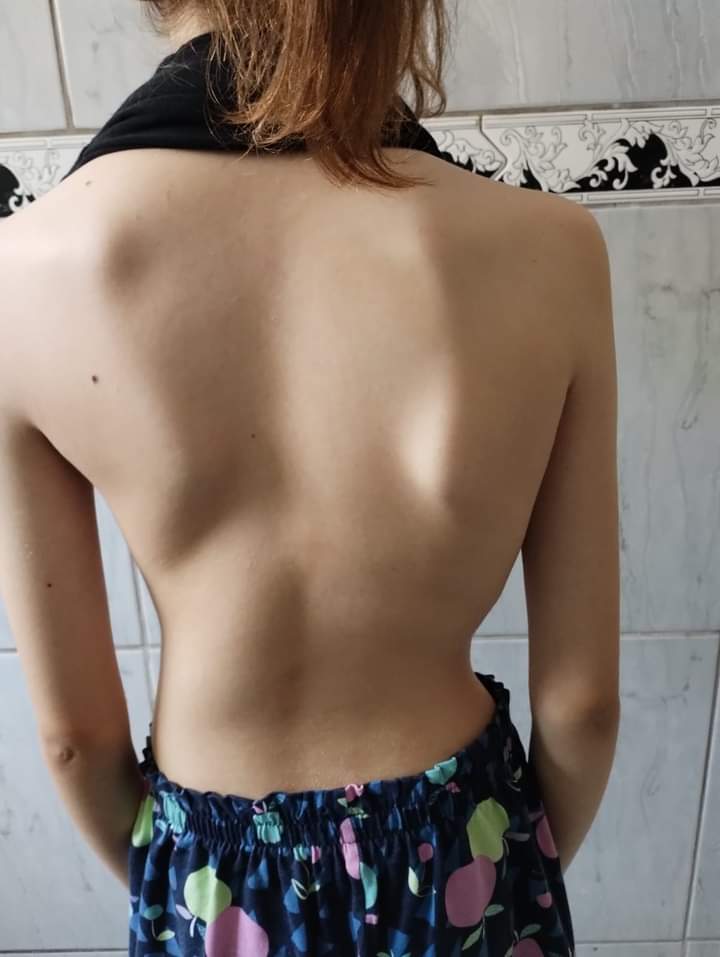

Há um ano mais ou menos descobrimos que tenho escoliose na coluna com uma curvatura mais de 39 graus. Já fiz muitas sessões de fisioterapia recomendada pelo médico, mas de nada adiantou. Minha mãe já fez tudo ao alcance dela, passei no núcleo com a ortopedista Jenifer. Ela me encaminhou para a regional porque está avançado meu caso, e pode prejudicar os meus órgãos, principalmente o pulmão, tenho muita dor, não consigo dormir, os medicamentos que tomo para dor não resolvem e podem me prejudicar futuramente..